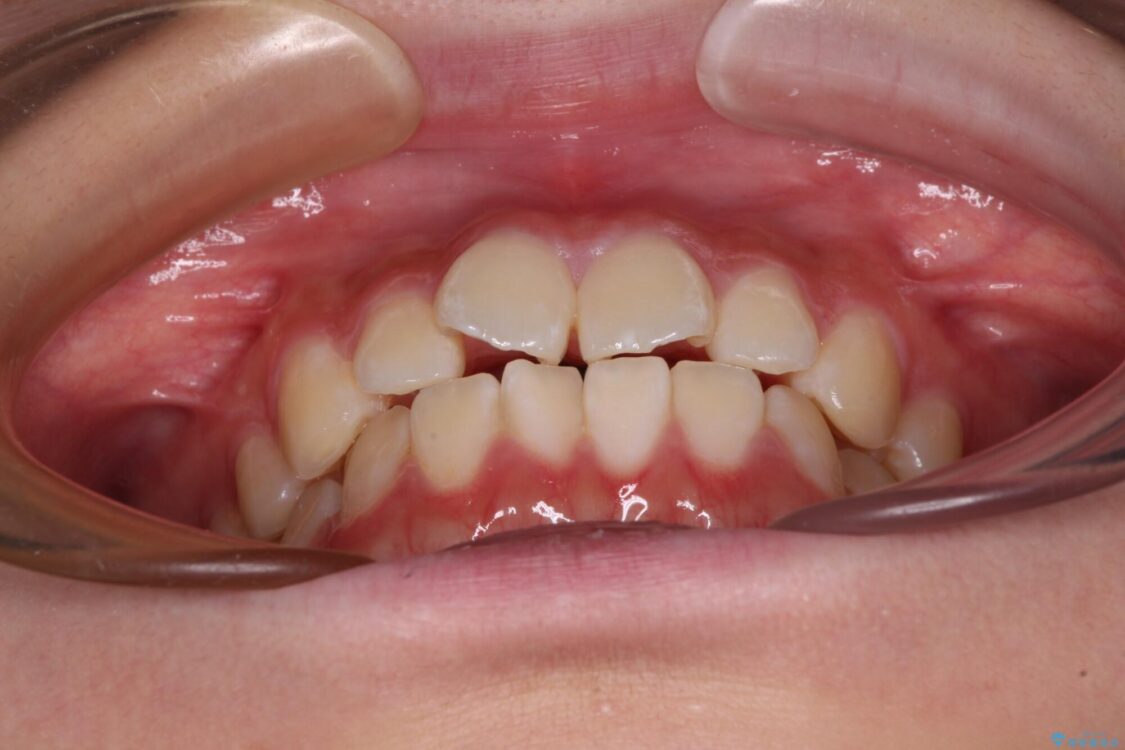

上下前歯のねじれを気にして来院された患者様です。

ワイヤー矯正でもマウスピース矯正でも対応可能でしたが、マウスピース矯正の自己管理が面倒であること、上顎前歯の捻転が著しいことから、ワイヤー矯正での治療を希望されました。

治療前

• インビザラインは使える自信がない ワイヤー装置にて矯正治療 治療前画像